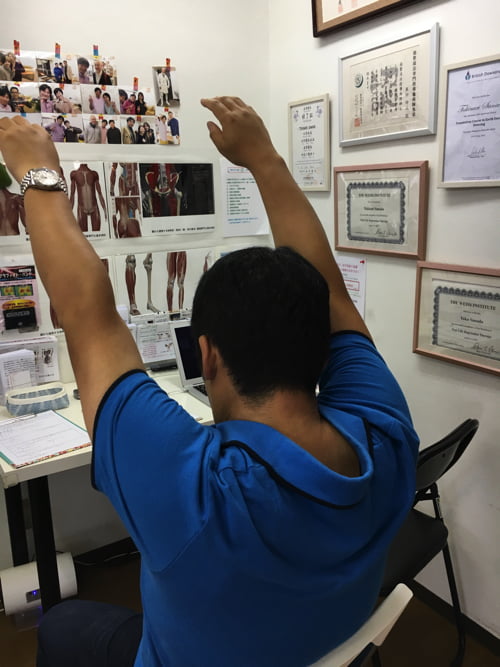

施術後すぐに、腕はここまで上がるようになりました。

今まで硬直やヨジレ、ズレがあった肩関節周辺は

筋肉や腱の硬直やヨジレのクセが付いていて

何事もなかったようになるには、少し時間がかかります。

少し違和感ある感じですが、ストレッチを続けていけば

どんどん楽になっていきます。